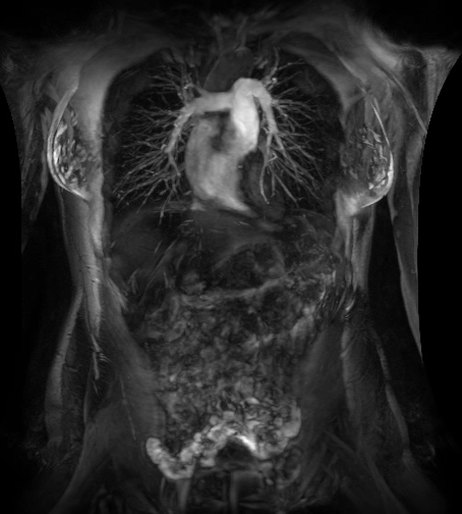

在乳腺M(fèi)R檢查中,SIGNAWorks?通過可調(diào)節(jié)線圈元件使得乳腺成像實(shí)現(xiàn)定量化和個(gè)性化,從而實(shí)現(xiàn)精準(zhǔn)醫(yī)療。創(chuàng)新型應(yīng)用——用于超快速動(dòng)態(tài)掃描的DISCO,用于高分辨率形態(tài)成像的Cube T2 with HyperSense和Cube T2 HyperCube,縮短了掃描時(shí)間并促進(jìn)了擴(kuò)散技術(shù)(Focus和MUSE)的發(fā)展,利用與BIRADs一致的CADStream來探測(cè)組織特征和分析。